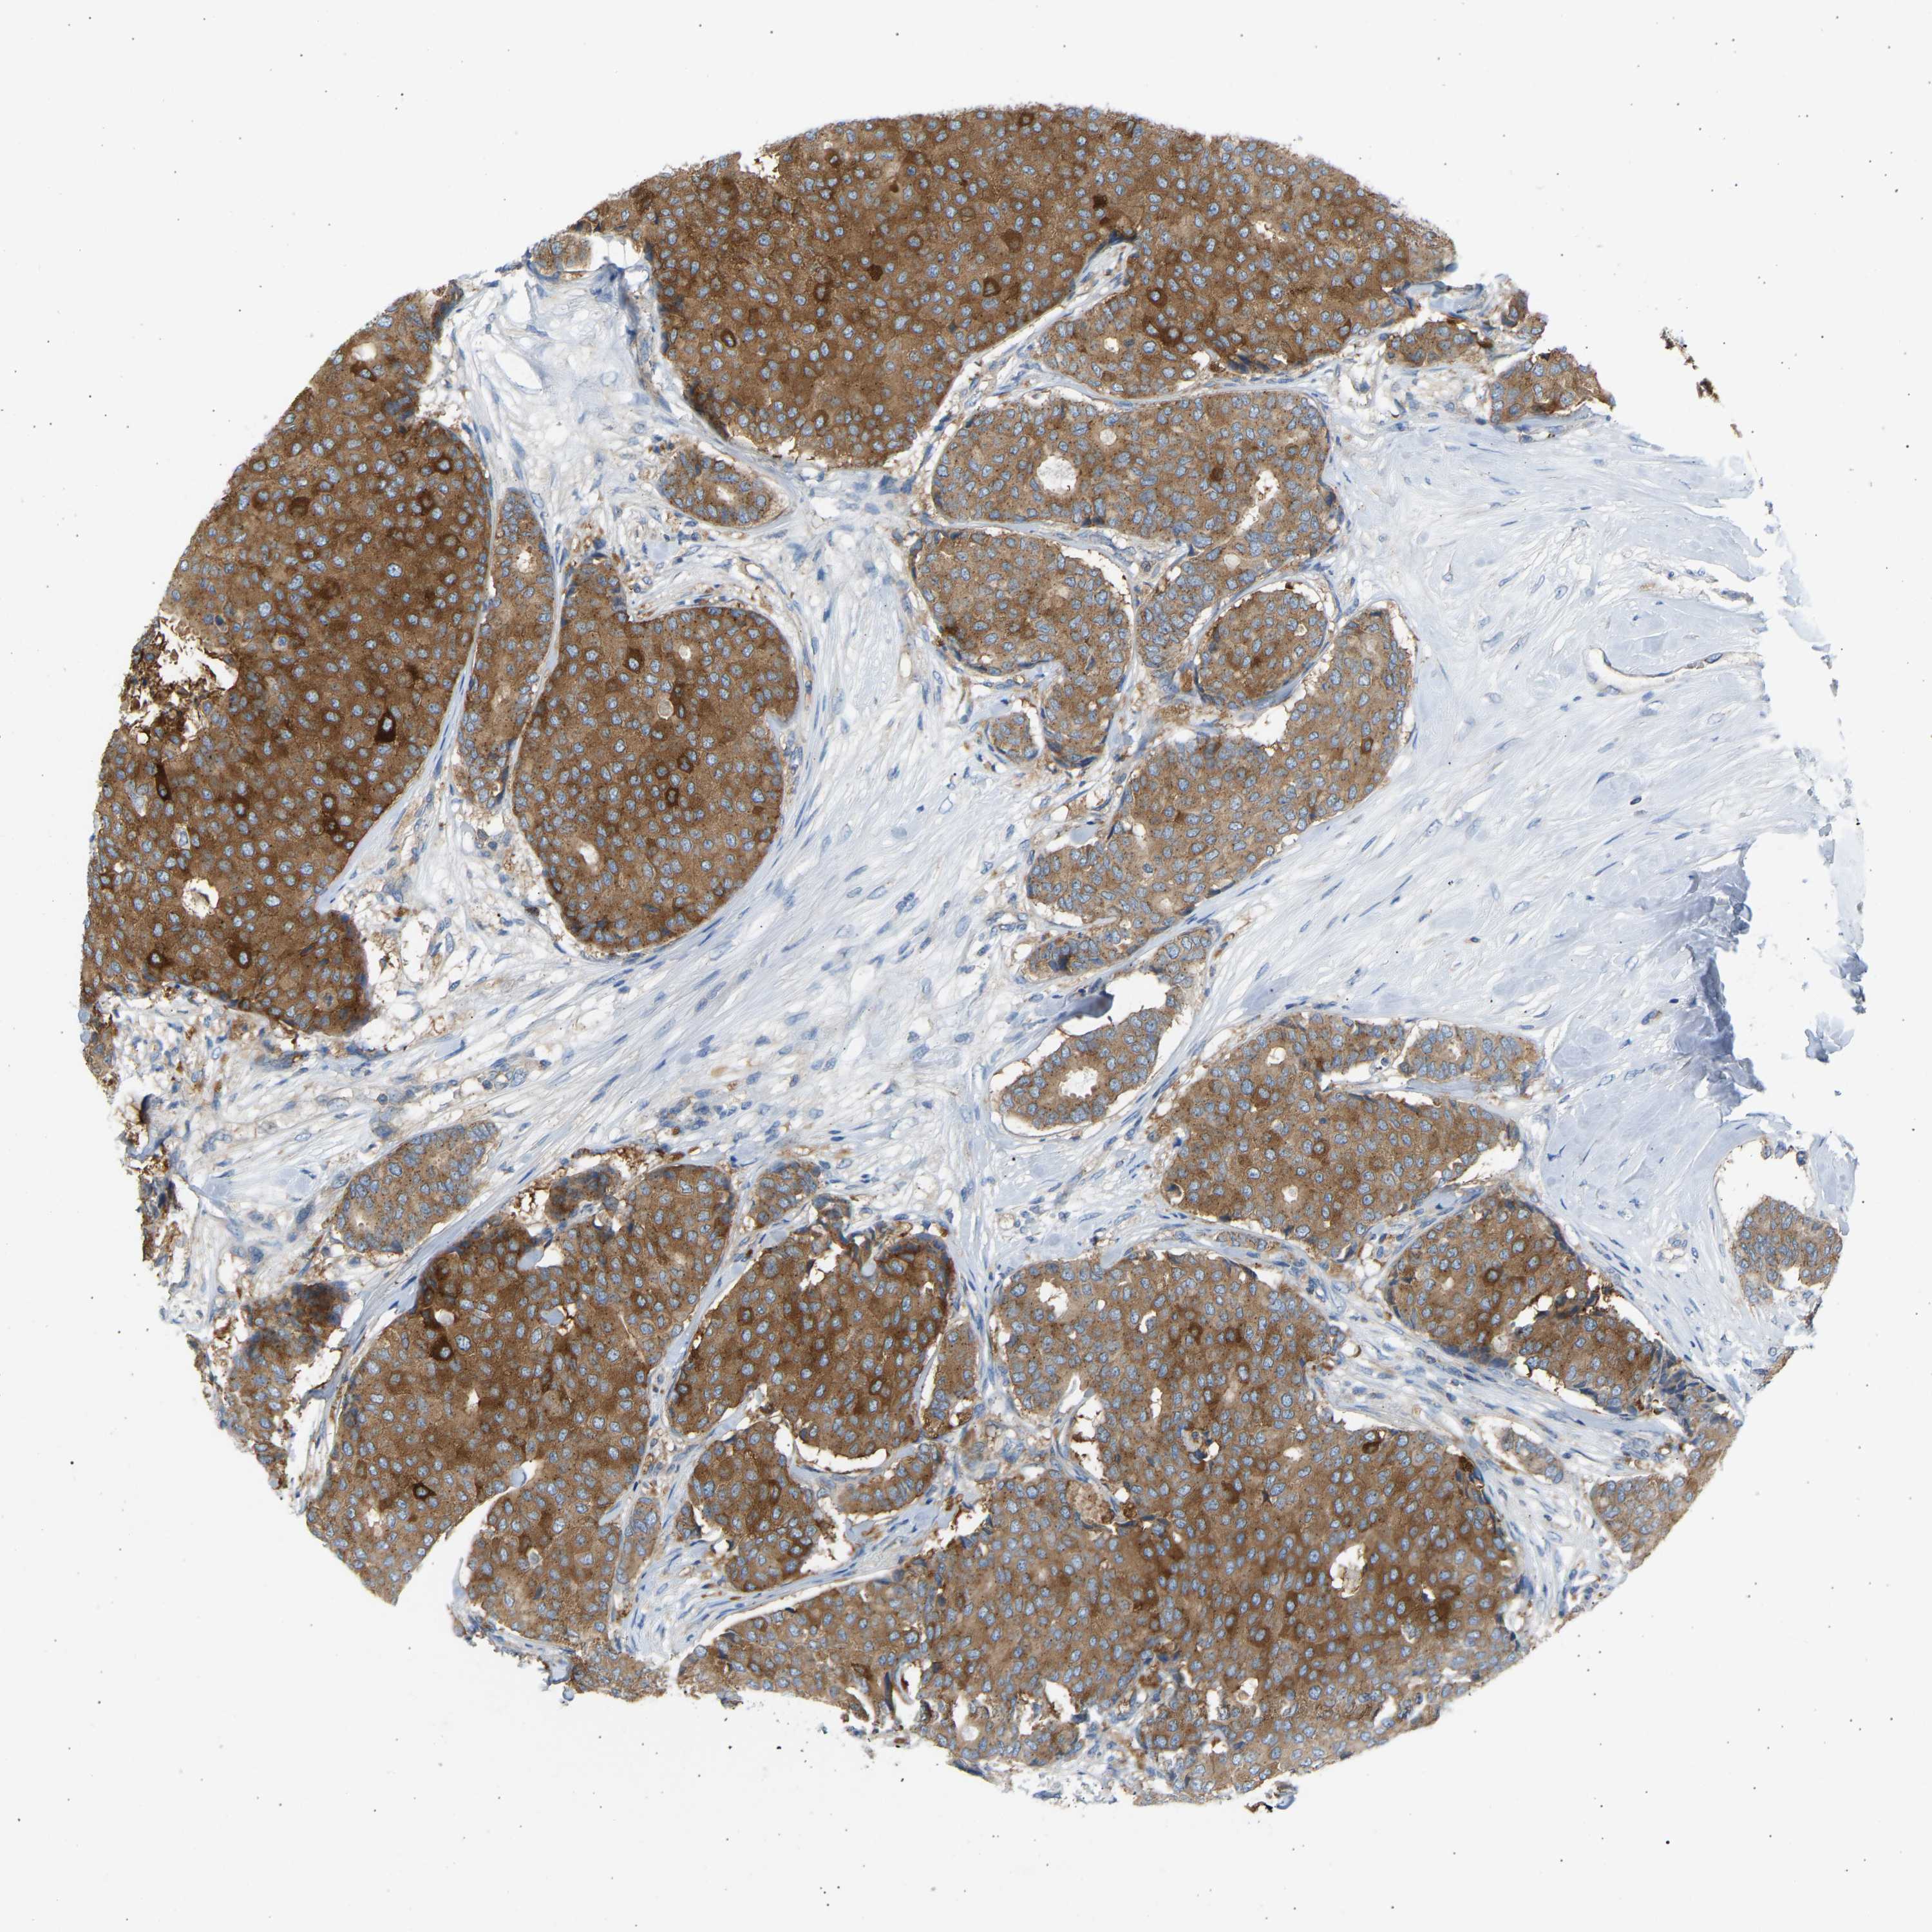

CANCER BREAST CANCER Show tissue menu

BRCA TCGA BRCA VALIDATION PROTEIN EXPRESSION

ANTIBODIES

AND

VALIDATION